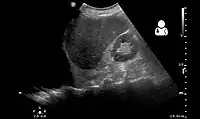

Ultrasonography may be used to detect hemothorax and other pleural effusions. This technique is of particular use in the critical care and trauma settings as it provides rapid, reliable results at the bedside.[23] Ultrasound is more sensitive than chest x-ray in detecting hemothorax.[25] Ultrasound can cause issues in people who are morbidly obese or have subcutaneous emphysema. When CT is unavailable in the current setting or the person cannot be moved to the scan, ultrasound is used.[3]

-

Ultrasound scan of the chest showing a left-sided hemothorax -

Ultrasound can detect blood in the pleural cavity. Blood in the thorax is shown by a uniform area without flocculation.[40] Pleural effusions without blood are usually hypoechoic. Echogenicity is indicated by cellular debris and/or fibrin. Bloody pleural effusions are shows by a swirling, hyperechoic pattern.[38] When a stethoscope is used (auscultation), the heartbeat sounds are faint. When percussion is performed, it produces a dull area. However, especially in traumatic cases, percussion may be painful. Although nonspecific, physical examinations may show reduced lung sounds and muffled, widespread heart sounds. Similar signs and symptoms may occur when other fluids are in the pleural cavity.[40]